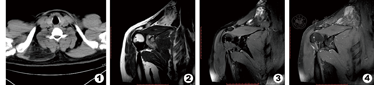

患者,男,36岁,发现右肩背部肿块8月余,当时未予重视及特殊治疗,自觉肿块进一步增大,于2016年1月19日入院。查体:右侧肩背部可见局部皮肤隆起,表面无红肿破溃,可扪及一肿块,大小约8 cm×6 cm,质软,轻压痛,活动度好,与周围界限清楚。入院查血常规、凝血未见明显异常。CT平扫表现:右侧岗上肌、斜方肌、肩胛提肌间隙内软组织及脂肪混合成分肿块,脂肪成分为主,CT值约-68 HU,大小约7.2 cm×4.6 cm,边界尚清晰,见图1。MRI平扫+增强表现:右侧岗上肌、斜方肌、肩胛提肌间隙内可见一不规则软组织肿块,大小约7.4 cm×4.7 cm,边界尚清晰,信号不均匀,T1WI呈高信号,T2WI高信号,脂肪抑制序列部分区域呈高信号,增强后病灶明显强化,且强化不均匀,并见线样血管强化。见图2,图3,图4。

CT平扫通常显示一个边界清楚低密度为主的软组织肿块,与皮下脂肪接近但不完全相同,内部可见线样、曲线样分隔。增强后分隔可以强化。所有病例均为弥漫性增强,而内部高线性或曲线密度为内部血管[3]。本病例磁共振表现和文献报道一致[1,2],在磁共振T1WI SE序列,多为相对(皮下脂肪)轻度至中度低信号强度,少数混杂信号强度,但整体上仍略低于皮下脂肪(和白色脂肪相比,质子在棕色脂肪有不同旋磁比和进动频率)。T2WI SE图像显示稍低信号,多数信号强度接近脂肪。STIR和T2脂肪抑制序列显示部分区域脂肪抑制,部分区域的信号强度高于皮下脂肪。MR增强,通常是均匀或不均匀的强化。